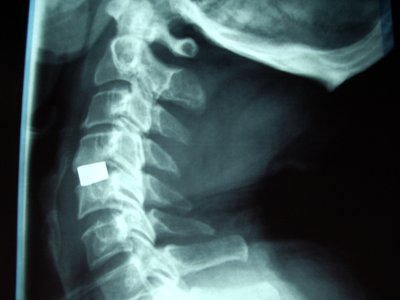

• Tratamiento quirúrgico de la Hernia Discal Cervical (prótesis rígidas y móviles).

Columna cervical